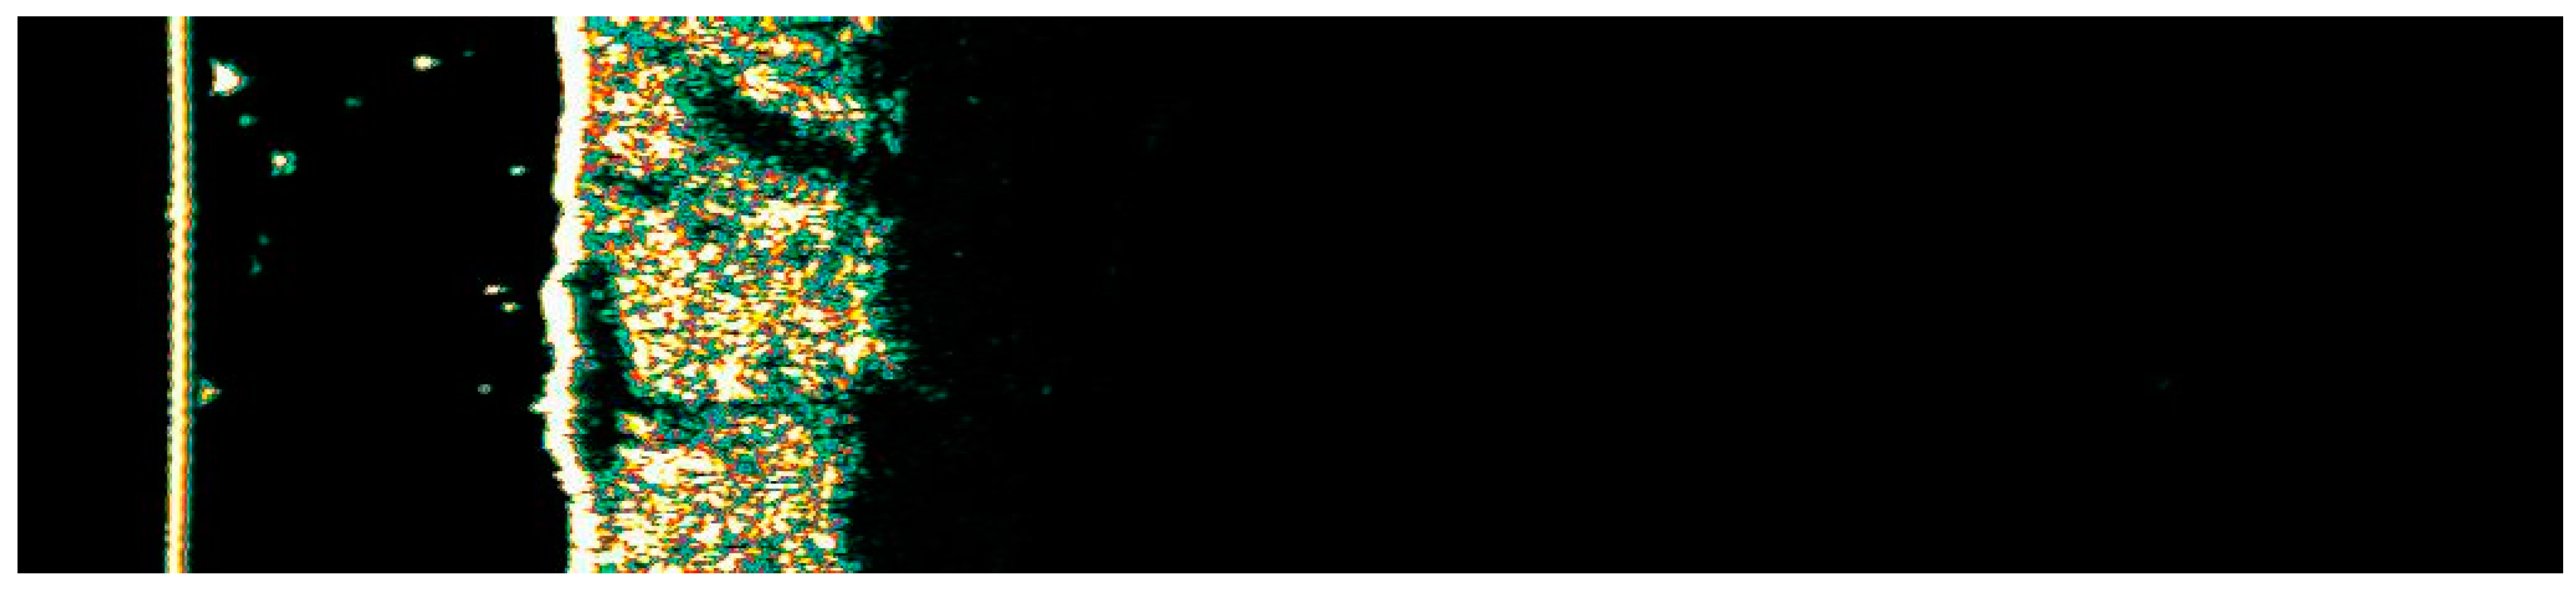

3.1. Clinical and Dermoscopic Involution of HIFU-Treated Basal Cell Carcinoma

| Number of Changes | Vascular Patterns | Pigment Structures | Non-Pigmented Structures | ||||||||||||||||

|---|---|---|---|---|---|---|---|---|---|---|---|---|---|---|---|---|---|---|---|

| Ambrozing Linear | Short Linear | Loop-like Linear | Bent Linear | Clod-like Linear | Radially Arranged | Segmentally Arranged | Reticular | Segmentally Arranged Linear | Radially Arranged Linear | Angular Linear | Small Gray-Blue Globules | Large Gray-Blue Globules | White Lines | Small White Structureless Areas | Pink Structureless Areas | White-Yellow Globules | Orange Globule–Crust | Rosettes | |

| 1. | X | X | X | X | 1 | ||||||||||||||

| 2. | X | X | X | 2 | |||||||||||||||

| 3. | X | 1 | |||||||||||||||||

| 4. | X | 2 | |||||||||||||||||

| 5. | X | 1 | |||||||||||||||||

| 6. | X | X | 2 | ||||||||||||||||

| 7. | X | 1 | X | ||||||||||||||||

| 8. | X | X | 2 | ||||||||||||||||

| 9. | X | X | 2 | ||||||||||||||||

| 10. | 1 | X | |||||||||||||||||

| 11. | X | X | 1 | ||||||||||||||||

| 12. | X | 1 | |||||||||||||||||

| 13. | X | X | 2 | ||||||||||||||||

| 14. | X | X | 1 | ||||||||||||||||

| 15. | X | X | 1 | ||||||||||||||||